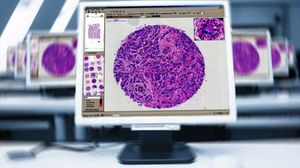

módulo de software de análisis de imágenesQuantCenter

... QuantCenter es una plataforma de análisis de imágenes de módulos múltiples diseñada para la cuantificación de cortes completos en histopatología y patología molecular. Gracias a su amplia gama de módulos ...

3DHISTECH Ltd.

... MembraneQuant es una aplicación de software de detección de membranas celulares que puede utilizarse para la cuantificación de muestras histológicas teñidas con IHC. Este módulo mide la morfología celular ...

3DHISTECH Ltd.

... integración de un marco de gestión de portaobjetos, una aplicación avanzada de visualización digital de portaobjetos y un software de examen flexible, 3DHISTECH establece un entorno de aprendizaje digital para histología, ...

3DHISTECH Ltd.